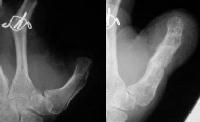

The initial lawnmower injury..

Treated with completion of the thumb amputation, external fixation of the distal radius fracture and primary metacarpophalangeal arthrodesis of the fingers.

Following this, the thumb soft tissue cover was inadequate and was augmented with a groin flap.